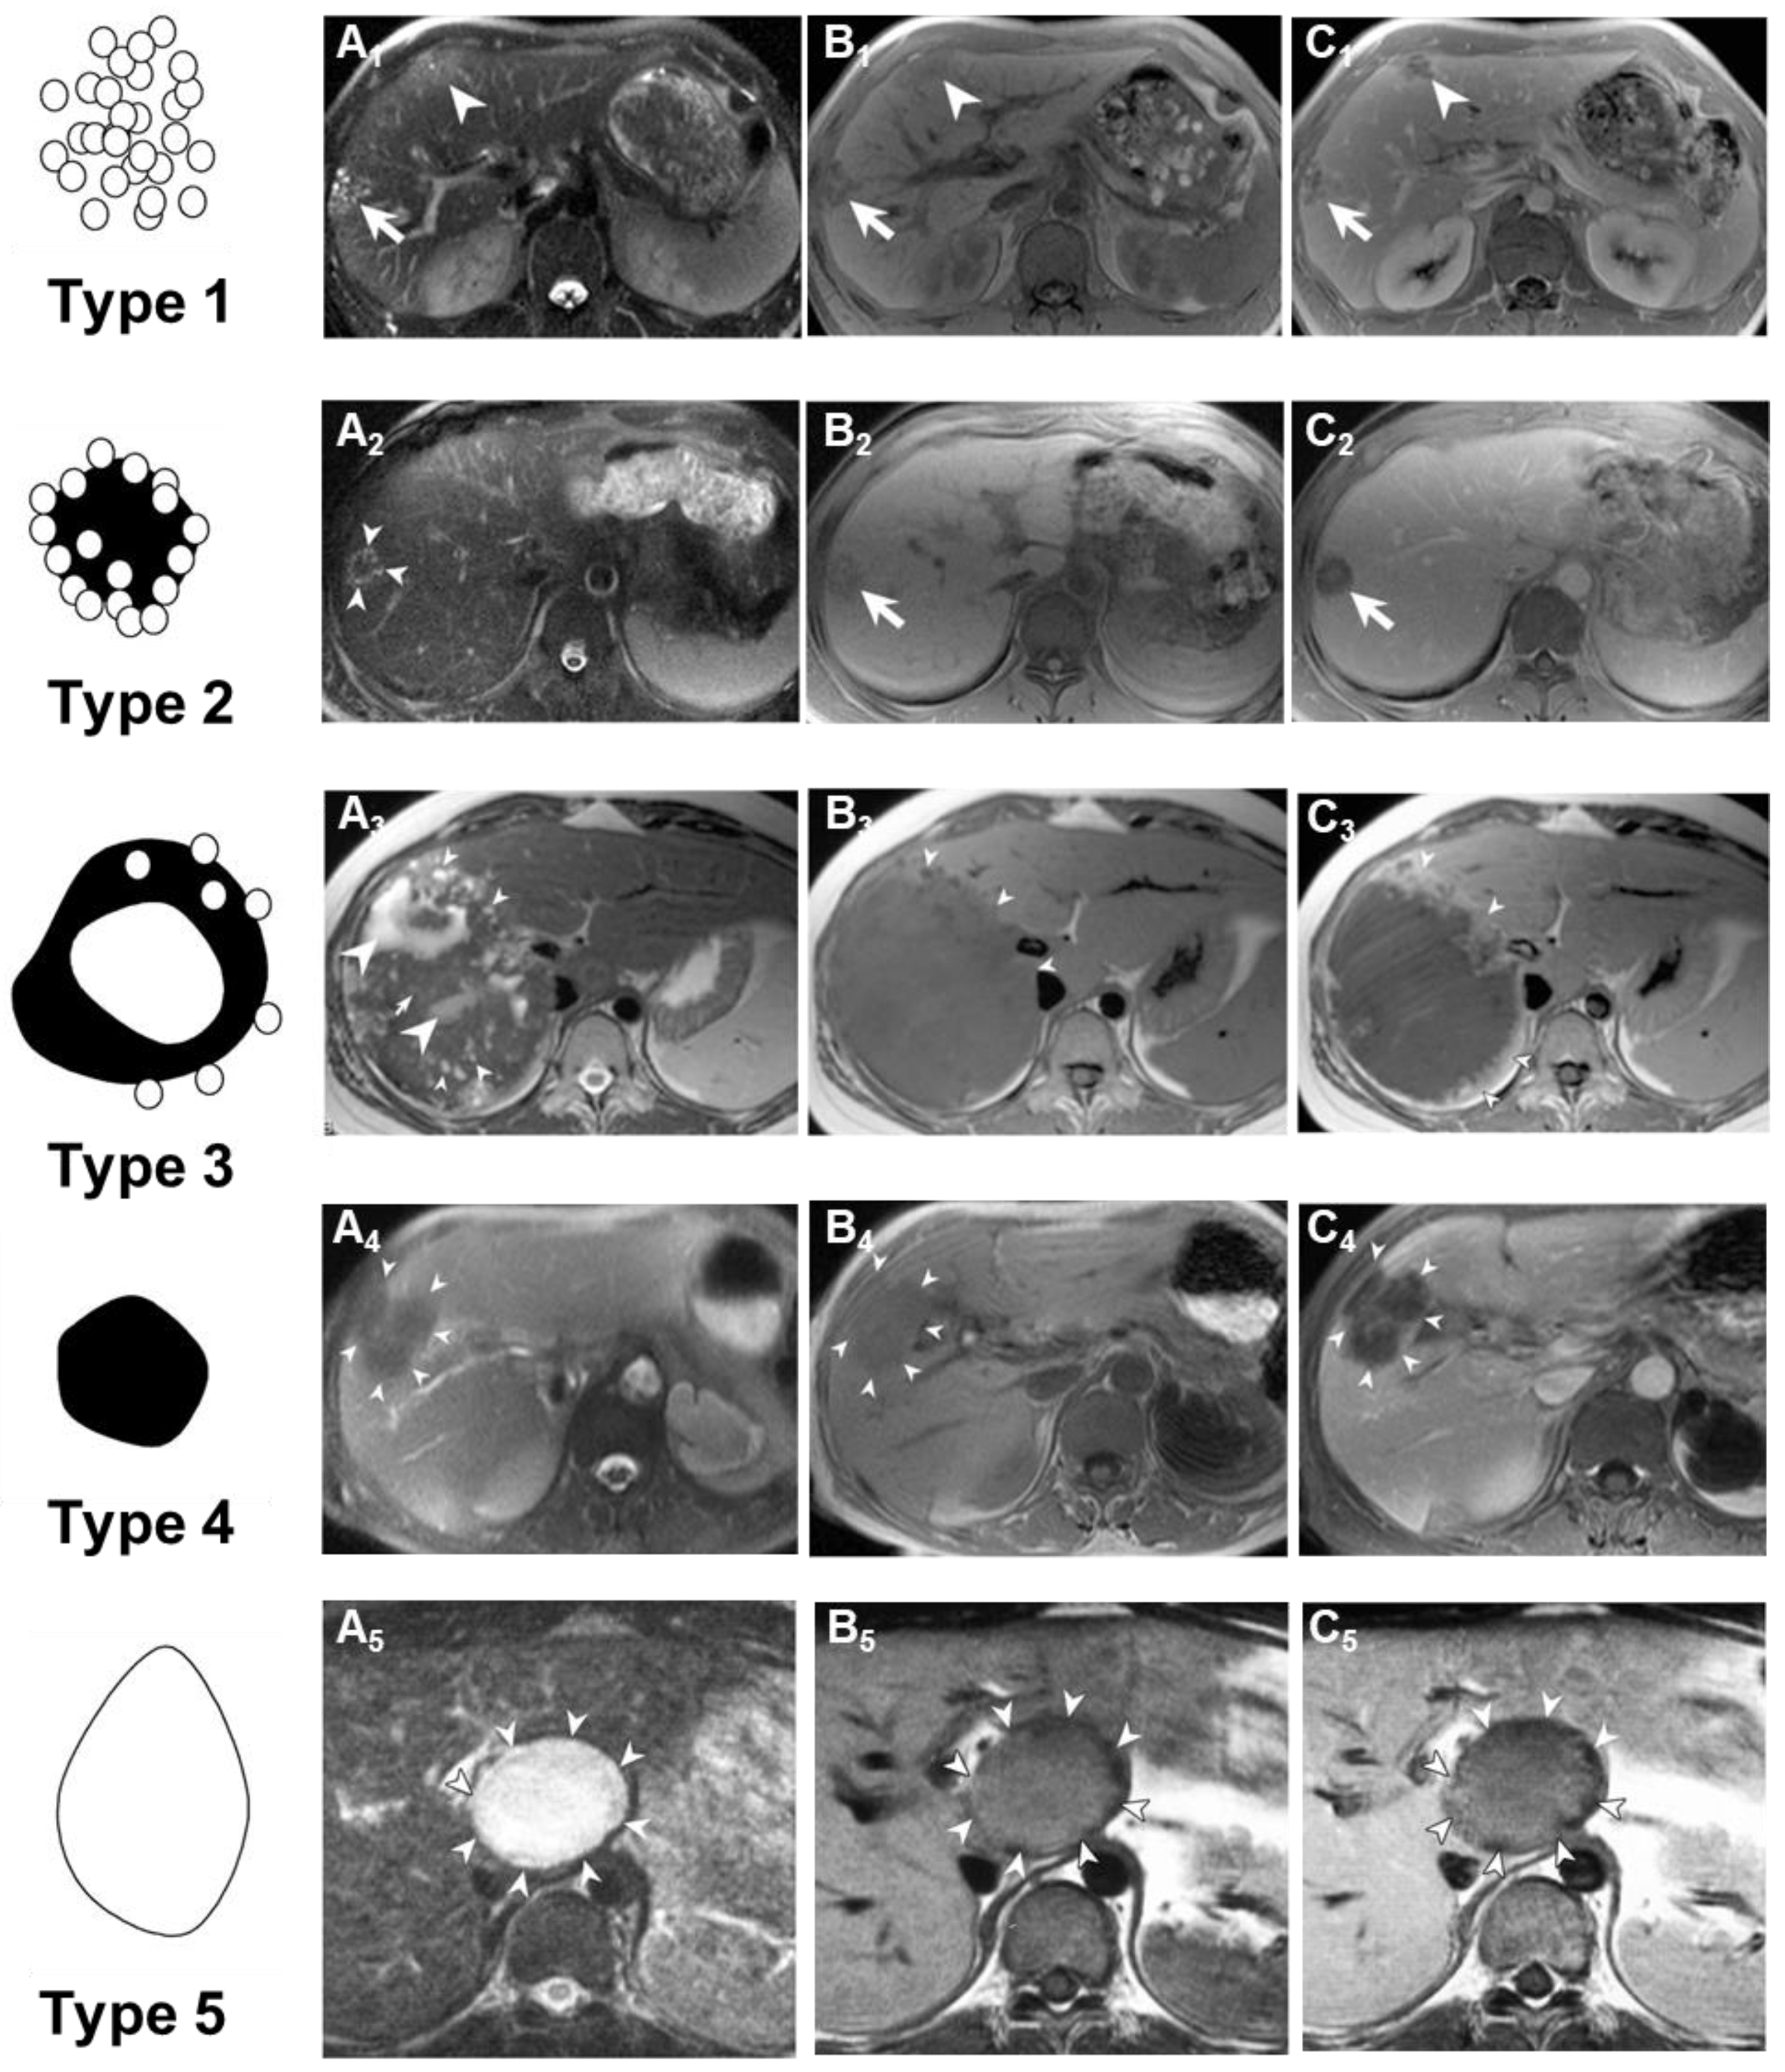

In 2003, Kodama and colleagues classified the MRI imaging results of patients with AE (Figure 7) [133]. They classified AE into five types based on its imaging manifestations on MRI: Type 1 consists of multiple small round cysts without a solid component; Type 2 features multiple small round cysts with a solid component; Type 3 is characterized by a solid component surrounding large and/or irregular cysts with multiple small round cysts; Type 4 comprises a solid component without cysts; and Type 5 is a large cyst without a solid component. The reliability of Kodama’s classification is excellent and has received widespread recognition, allowing for the identification of five types of liver lesions based on morphological features on T2-weighted MRI sequences. Brumpt et al. further refined the Kodama classification by subdividing Type 3 into IIIa with microcysts and IIIb without, based on the crucial role of microcysts in therapeutic decision-making for AE lesions [136]. T2-weighted MRI imaging exhibits better imaging performance in the early diagnosis of AE, compared to CT or US. In a 74-year-old male patient, seven years after resection of rectal cancer, CT scans and ultrasound images revealed two small, uniform low-density and hypoechoic lesions in the liver, respectively. These lesions were later histologically confirmed as early but active AE. Abdominal MRI, on T2-weighted images, demonstrated two isointense tumor lesions with small areas of high-signal intensity at their centers. The MRI findings seemed to accurately reflect both the macroscopic and microscopic manifestations of early AE, with each liver lesion containing an active cyst at its center [137].